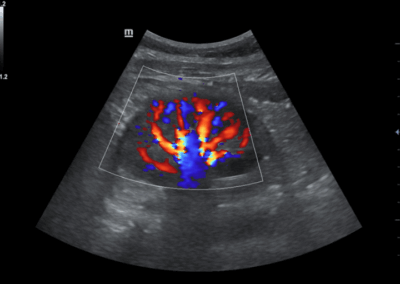

Los sistemas ecográficos estándares disponibles en la actualidad generalmente permiten un diagnóstico básico, pero carecen de funcionalidades avanzadas. Ahora, el DC-30 FullHD es la respuesta perfecta para un rendimiento de imagen de alta calidad, con una pantalla táctil de 21,5 pulgadas y funciones avanzadas como Auto IMT, iScape, elastografía Natural Touch, imágenes con contraste UWN e imágenes Doppler tisulares en el ámbito de las imágenes generales, y Smart OB, Smart face e iLive en el ámbito de la obstetricia.